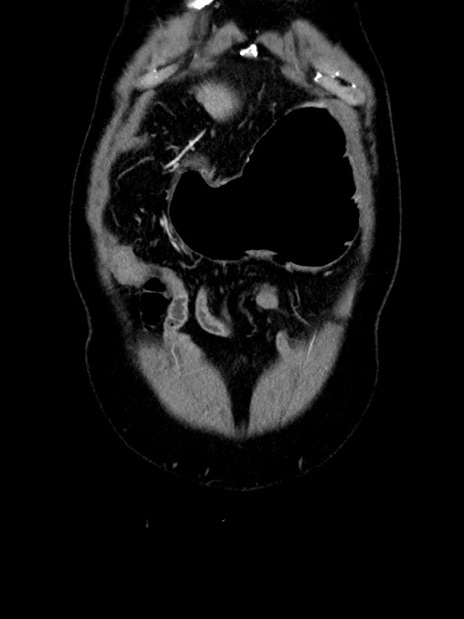

症例35(冠状断像)

症例

【症例】70歳代 男性

【主訴】腹部膨満、嘔吐

【現病歴】昨日より腹部膨満感出現。本日増悪し、仙痛出現。嘔吐あり、受診。

【既往歴】糖尿病、胆摘後

【身体所見】BP 149/80mmHg、HR 74/min、BT 35.9℃、腹部:膨満、軟、圧痛なし。腸雑音減弱あり。上腹部正中切開瘢痕あり。

【データ】WBC 13500、CRP 1.72

横断像